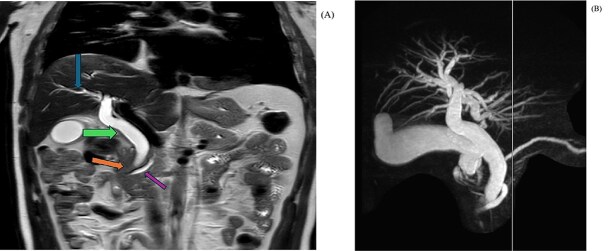

In coronal view at the same level (Fig. 3), a MRI T2 Haste shows abrupt cut-off of the distal CBD (orange arrow) with a dilated common bile duct (green arrow) and a mild degree of intrahepatic biliary dilatation (blue arrow). The CBD proximal to the level of obstruction measures approximately 12 mm in caliber. Mild dilatation of the pancreatic duct is noted giving the double duct sign (purple arrow) with the main pancreatic duct measuring approximately 6.7 mm in the region of the pancreatic head.

MIP image (B) from MRCP confirms the cut off at the distal CBD, with severe dilatation of the extrahepatic and intrahepatic biliary tree, as well as dilated pancreatic duct.